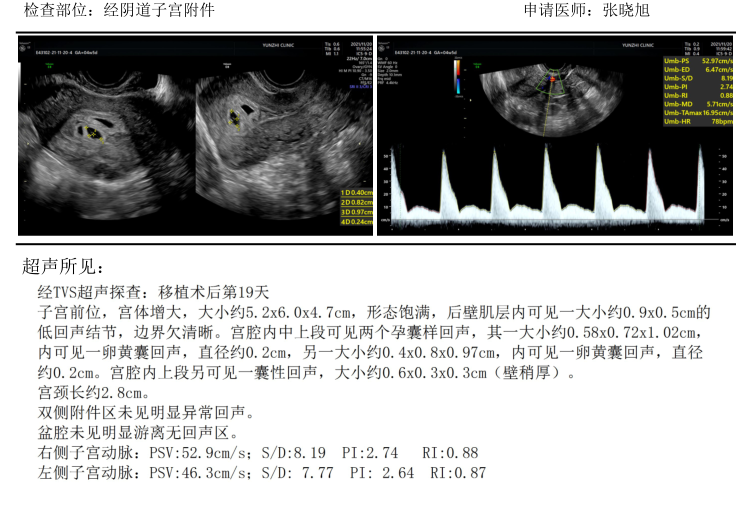

看着超声检查结果,34岁的曹女士(化名)喜极而泣。

图片

检查结果